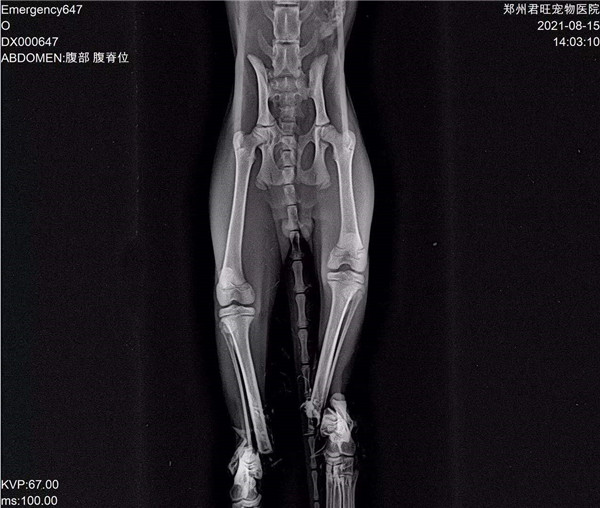

郑州市君旺宠物医院的翟医生,望着眼前面目全非的九福,微微锁起了眉头,简单检查过之后,就得出了判断:九福是被人虐待了。因为它的四条腿均是对称性骨折,两只前腿更是粉碎性骨折,满口牙也被拔掉了。“这绝对不是车祸,或者动物撕咬造成的,只能是人。”